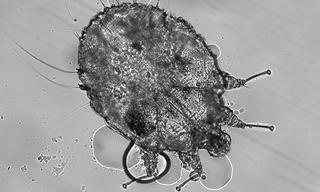

Liên tục tiếp nhận các trường hợp bị ghẻ sinh dục